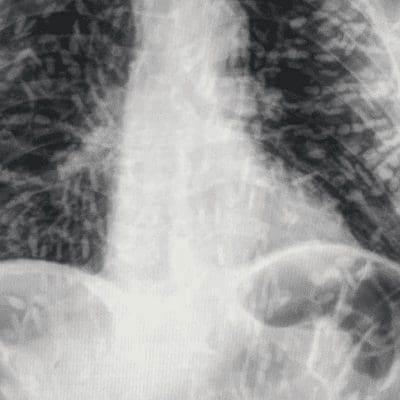

O diagnóstico da cisticercose disseminada é feito por meio de exames de imagem, como raio-X, tomografia ou ressonância magnética, que mostram as lesões causadas pelas larvas nos órgãos afetados. O tratamento consiste no uso de medicamentos antiparasitários e anti-inflamatórios, além de medidas de suporte para aliviar os sintomas. Em alguns casos, pode ser necessária a cirurgia para remover os cisticercos.